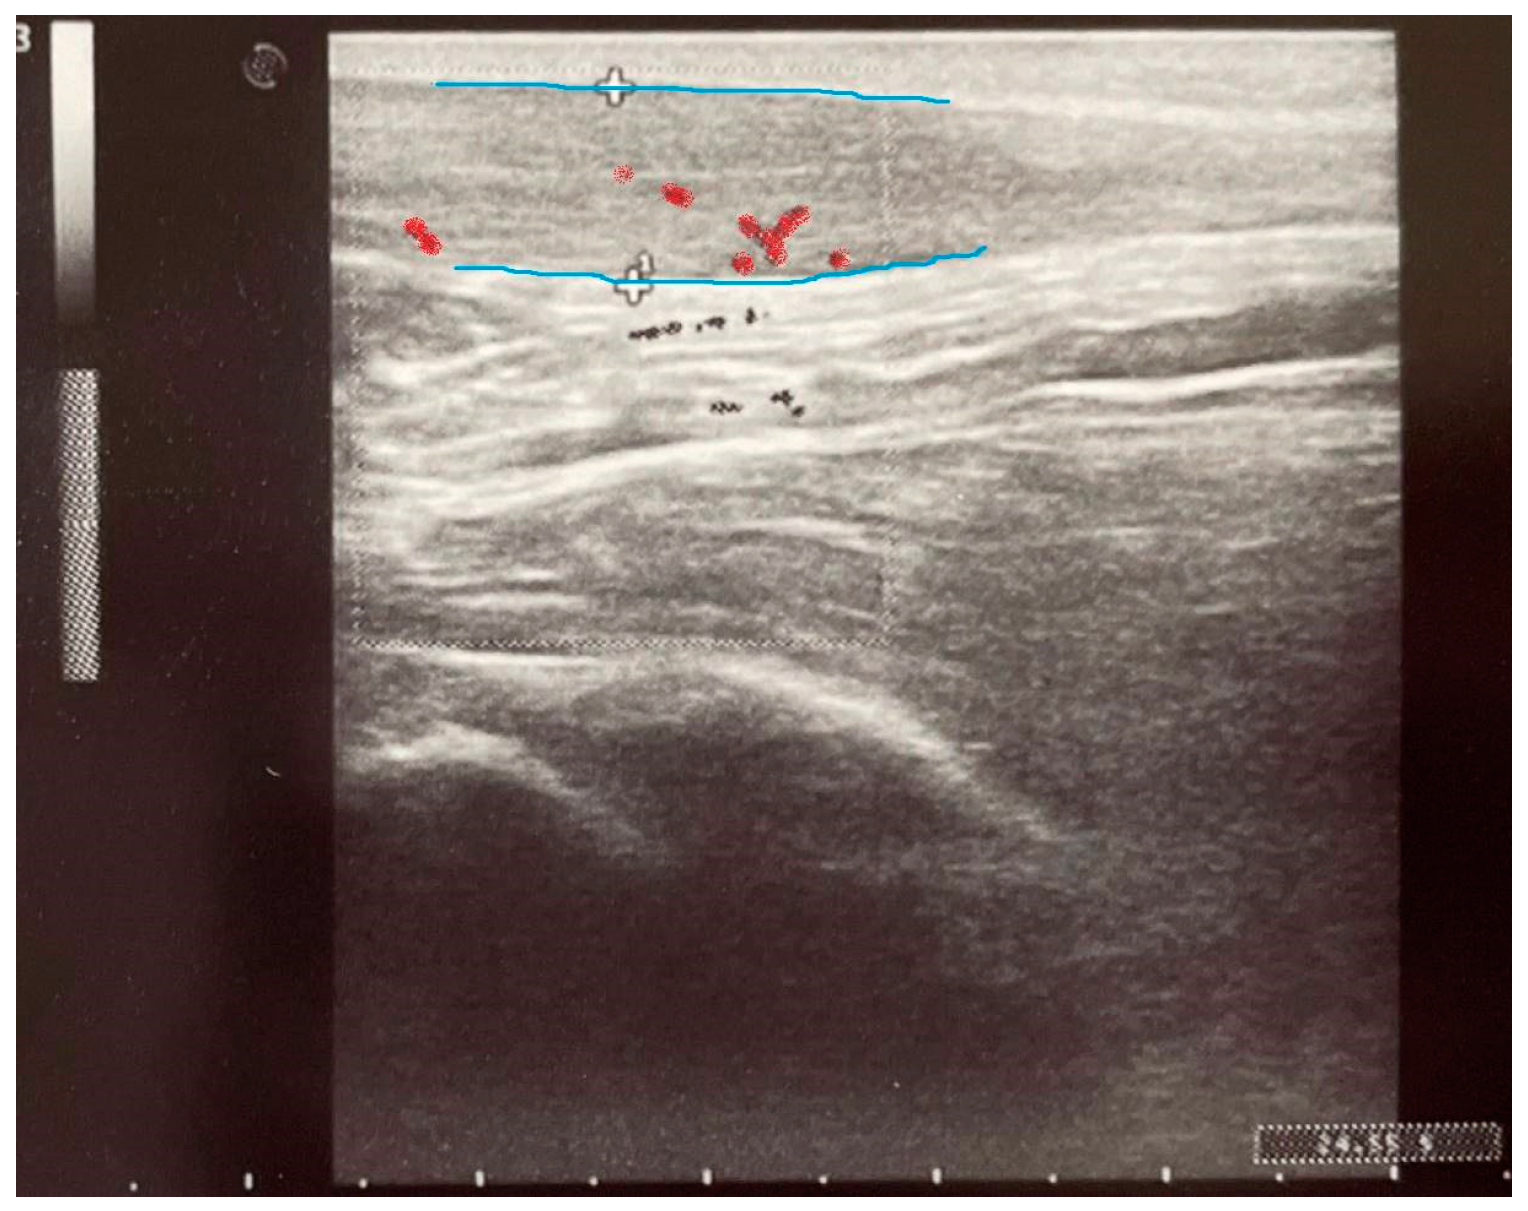

2.4. Paraclinical Evaluation—Ultrasound

| Achilles Tendon Thickness (Left Leg) [mm] | Achilles Tendon Thickness (Right Leg) [mm] | |

|---|---|---|

| Induction | ||

| Group C | 4.327 ± 0.502 | 4.313 ± 0.4389 |

| Group ES | 4.500 ± 0.5907 | 4.480 ± 0.3676 |

| Day 8 | ||

| Group C | 5.173 ± 1.529 | 4.693 ± 0.7488 |

| Group ES | 5.470 ± 1.105 | 5.170 ± 0.7439 |

| 3 Months | ||

| Group C | 5.100 ± 1.144 | 5.100 ± 1.313 |

| Group ES | 5.830 ± 1.643 | 5.310 ± 0.7340 |